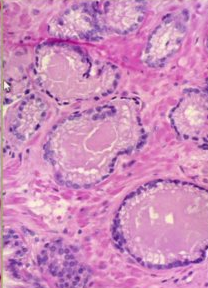

Collagenous Micronodules (pathognomonic feature of PCa)